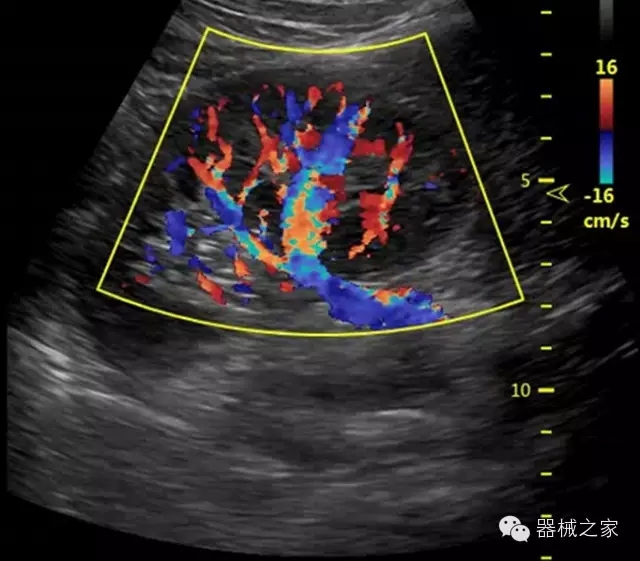

臨床圖片賞析

產(chǎn)品特點(diǎn)

優(yōu)異的成像技術(shù)

·智能微血流成像技術(shù):智能微血流捕捉技術(shù)可以提取出隱藏在背景噪聲中的弱血流信號,大大提高低速血流的敏感性;

全面的臨床解決方案

·移植S40高端臺式彩超高端平臺技術(shù),滿足超聲科腹部、淺表、婦產(chǎn)科、心血管、肌骨等應(yīng)用,提供超聲科完美解決方案;